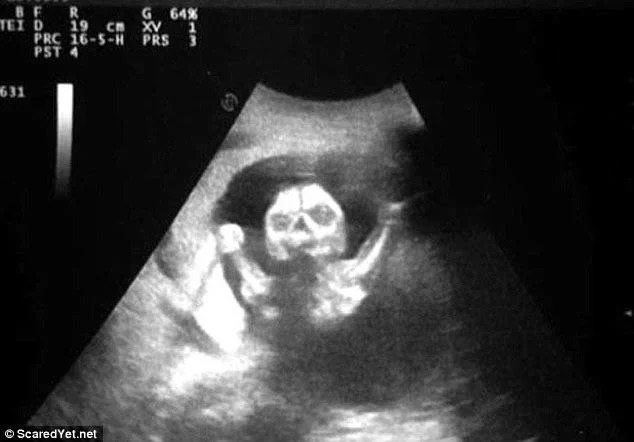

13. И теперь я думаю, какое имя дать моему будущему ребёнку